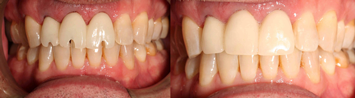

Clinical Example

Figure 26 shows a full-arch classic "All-on-X" case at presentation. The patient was a 66-year-old male with a mutilated dentition. The patient had lost vertical dimension and desired a fixed restoration. Options were discussed with the patient, including dentures, which the patient refused long term. The patient instead agreed to a plan to undergo extractions of his remaining dentition and have an immediate maxillary denture with five mandibular implants and an immediate mandibular hybrid denture. The practitioner worked with a laboratory that could provide a monolithic PMMA digitally milled denture. Two months following implant treatment of the mandibular arch, the patient had six maxillary implants placed with immediate denture conversion.

The workflow presented is a hybrid analog and digital approach.

Intra- and extraoral photographs, intraoral scans, and analog impressions were taken and a CBCT was acquired. A digital smile design was accomplished and records sent to the laboratory (Figure 27). The digital records and analog models were scanned and imported into the digital denture scanning software that was used to plan the denture. The denture plan was then imported into the implant planning software (Nobel DTX Studio, Nobel Biocare; alternatively: X-Guide, X-Nav Technologies; Implant Studio, 3Shape) to create the plan for the implants (Figure 28). Next, the plan was imported into the navigation software system of the navigation unit, and the practitioner was able to begin planning bone reduction and screw positions.

At the time of surgery, the maxillary dentition was removed, bone grafts were placed, and an immediate denture was relined in the predetermined occlusion using an occlusal stent. Next, a crestal incision was made in the mandible. The fixation screws were then placed below the level of the planned bone reduction. The tracker arm was placed on the platform of the screws and the nuts tightened to rigidly fixate the patient tracking arm. The tracker array was then tightened into place. The arm of the tracking array additionally assists as it retracts the lip. Next, the patient was registered anatomically by touching the teeth in the predetermined locations. A system check was performed to verify the accuracy of the tracking system. No refinement was necessary. Bone reduction was then accomplished using a straight handpiece under navigation, and the implants were placed. The prosthodontist then used temporary cylinders and picked up the positions of the implants using the milled mandibular transition appliance. The occlusal locks at the distal of the prosthesis assured that the correct vertical dimension was obtained (Fig- ure 29). The incision was closed, and the denture was finished in the laboratory and delivered the next morning.

The hybrid denture was delivered the next day. After 2 months, the patient was seen again, and the practitioner performed osteo- tomies and placed six maxillary implants. Figure 30 is a retracted view of the patient's dentition 1 week postoperatively. For both the mandible and maxilla together, the mean angular deviation was 2.08 (SD, 0.85), the mean platform deviation was 0.97 mm (SD, 0.43), and the mean apical deviation was 1.25 mm (SD, 0.44), which is within the expected range. With the help of dynamic navigation, the procedure was extremely successful. Figure 31 shows the patient's digitally milled PMMA prosthesis and soft tissue at 1 year postoperatively.

Fig 26. Mutilated dentition in an edentulous patient.

Figure 26

Fig 31. Final PMMA digitally milled prosthesis at 1 year postoperatively.

Figure 31